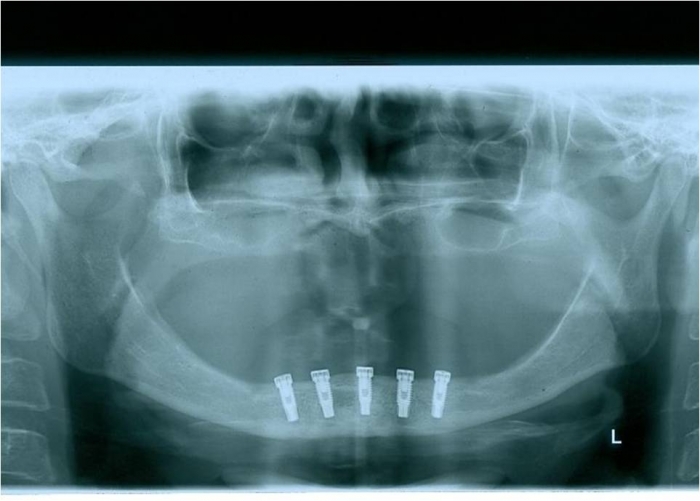

Raio x dos implantes